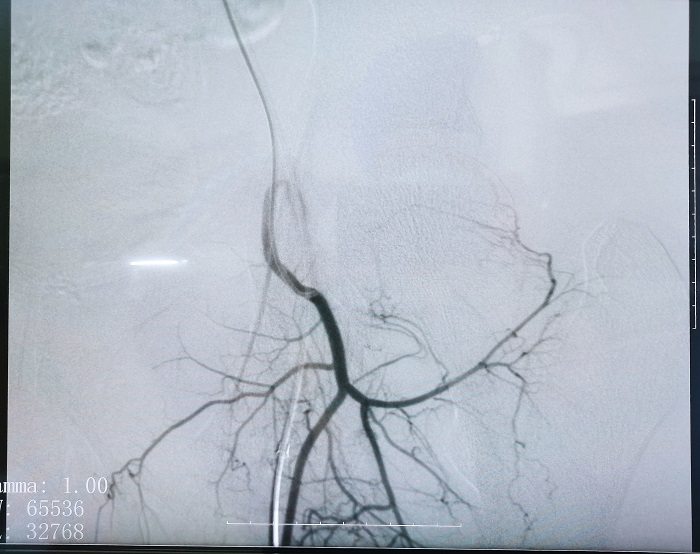

普愛平板介入中C在FTE手術過程中拍攝的造影圖像

若根據HSG的診斷,患者存在輸卵管積水,則可行輸卵管栓塞術(Fallopian tube embolization, FTE),通過介入手段,注入栓塞劑或使用彈簧圈等器材進行栓塞,可以有效地阻斷輸卵管內的血流和組織,從而治療輸卵管積水。這個過程通常是在X線或超聲引導下進行的,可以清楚地看到輸卵管的情況。

輸卵管栓塞的介入治療作為輸卵管積水的預處理是一項創新性的方法,也是行之有效的方法,所有操作都可在醫學影像設備下進行,定位準確、操作簡便。同時因為基本是微創手術,所以對卵巢功能無影響,可以有效改善輸卵管積水引起的癥狀,如腹痛、腹脹等,并提高患者的生育能力,對體外受精-胚胎移植(IVF-ET)的發展有新的突破,妊娠率有顯著性增加。